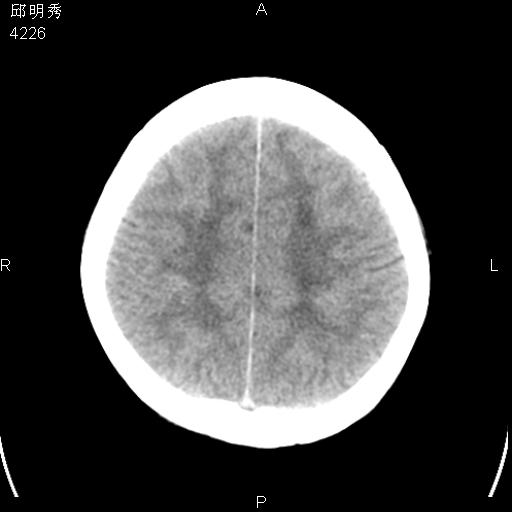

40f头晕十多天,右上肢麻木一天

脑白质变性或ms

脑白质脱髓鞘改变。

脑白质病;建议行mri检查。